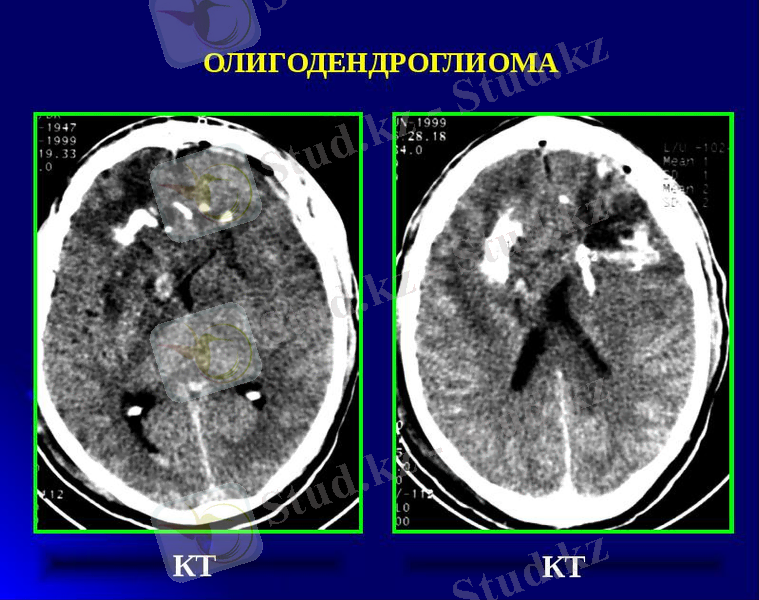

Олигодендроглиалық ісіктер. Ол негізінен аралары өте жақын, ядросы ірі, домалақ, ал ядро айналасында түссіз аймағы бар клеткалардан түзіледі.